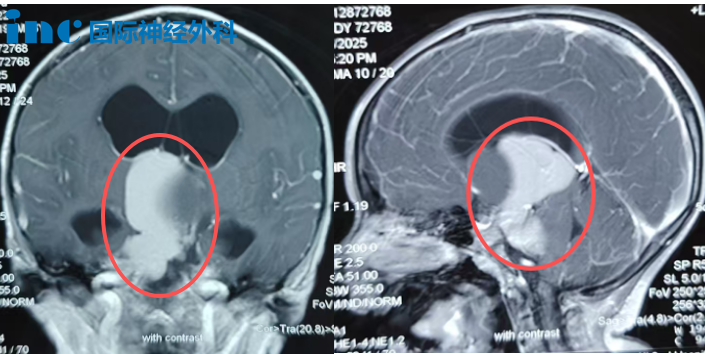

2024年12月,小安首次出现头痛症状,初诊被怀疑为鼻窦炎。直至今年上半年头痛复发,伴有不愿上学等表现,家人始觉异常。期间虽经历搬家环境变化,但间歇性头痛始终未引起重视。直至出现喷射性呕吐、头痛加剧、行走不稳等典型症状后,MRI检查才揭示鞍上延伸至第三脑室和桥小脑角区的巨大颅咽管瘤,并已继发脑积水。

十一月初,在多方咨询未果后,田先生于凌晨发出的求助得到了巴特朗菲教授的回应。教授明确表示:"手术具有必要性和可行性。当前脑积水易出现代偿失衡,需行急诊手术。基于四十余年手术经验,我对本次手术成功抱有充分信心。"

田先生一家始终坚持保障患儿未来生活质量的原则,不愿为追求全切而牺牲内分泌功能。巴教授详细说明手术需兼顾视路系统和内分泌功能保护,承诺将尽力保留重要血管神经结构。这番专业分析让家人看到了希望曙光,田先生感慨:"教授给予的希望之光让我们勇于尝试。与健康相比,其他都显得微不足道。"

由于术前近6cm肿瘤对视神经造成压迫,加之脑积水影响,患儿存在视野受限问题。但巴教授认为这属于可逆性损伤,经过数月休养有望逐渐恢复。家人用"抓虫子"的比喻鼓励小安,术后其四肢活动、神经功能、记忆思维等均保持良好状态。